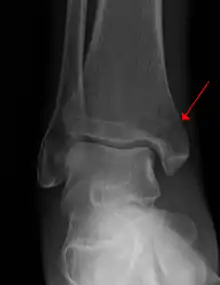

Example of an intraarticular fracture of the medial malliolus extending in the talocrural ankle joint.

An intraarticular fracture is a bone fracture in which the break crosses into the surface of a joint. This always results in damage to the cartilage.[1] Compared to extraarticular fractures, intraarticular have a higher risk for developing long-term complications, such as posttraumatic osteoarthritis.[2] Treatment considerations include restoring joint surface congruity and maintaining joint alignment and stability.